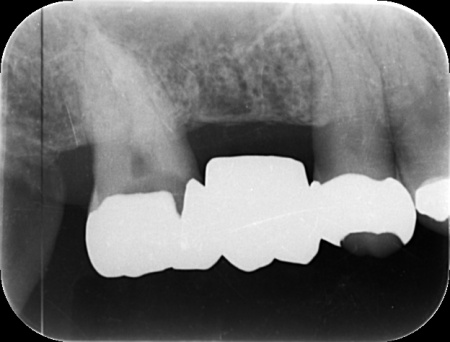

神経が温存できていることを確認できたため精密な型取りを行い、虫歯の再発リスクが低く強度も高いセラミックのジルコニアでブリッジを新たに作製しました。

完成したブリッジを装着し、痛みや違和感がなく噛み合わせや見た目にも問題がないことを確認して、治療を終了しました。